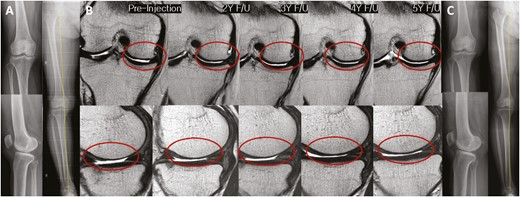

2022年5月14日,韓國江東慶熙大學醫院骨科在行業期刊《干細胞轉化醫學》上發表了一篇關于《關節內注射間充質干細胞治療膝骨關節炎的安全性和有效性:5年隨訪研究》的研究成果。【4】

關節內注射間充質干細胞治療膝骨關節炎的安全性和有效性:5年隨訪研究

招募了11名膝關節骨關節炎患者,并在單次關節內注射自體高劑量 (1.0×108?) ADMSCs 的5年隨訪期間進行了系列評估。

2.放射學結果評估

• 注射后5年內未見內翻力線或KL等級分布明顯惡化(圖3)。

• 系列MRI檢查顯示,注射后3年內MFC軟骨缺損面積呈減少趨勢,治療后5年內未見明顯惡化(圖 4)。

放射學結果評估

圖 4

• 內側間室軟骨WORMS評分在注射后2至3年間均有明顯改善(2年,P=0.029;3年,P=0.031)(表3)。

• 治療后3年內,總體WORMS顯示出顯著改善,從73.4±27.8顯著下降至70.5±26.8(6個月;P= 0.020)、65.5±29.4(2年,P=0.016)和66.5±30.7(3年,P=0.041)(表3)。

• WORMS子評分還顯示,在注射后2至3年內、注射后2年內和注射后3年內,總軟骨狀態、骨髓水腫和滑膜炎均有顯著改善。

綜上所述,VAS和總WOMAC評分在注射后6個月以及直到最新隨訪時均顯著改善。總WORMS在注射后3年內顯著改善。

單次關節內注射自體高劑量ADMSCs可在5年內提供安全的臨床改善,且不會出現放射學加重。此外,骨關節炎膝關節的結構變化在長達3年的時間內顯示出顯著改善,這表明它可能是膝關節OA患者的疾病改良治療的一種可能選擇。